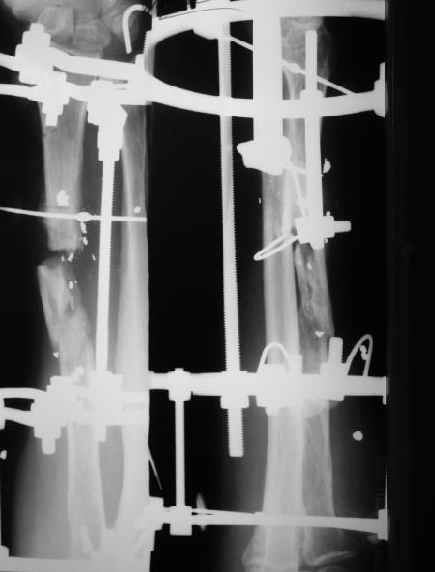

В приложении - снимок по окончании дистракции, и после смены аппарата на стержень (довольно толстый, 5 мм). С входом в канал на центральном отломке пришлось малость попотеть, промежуточный отломок его прикрывал. Но все-таки удалось закрыто проколупать. Надеюсь, дня через 3-4 после операции можно будет передать пациента нейрохирургам. Буду признателен за критику и комментарии.